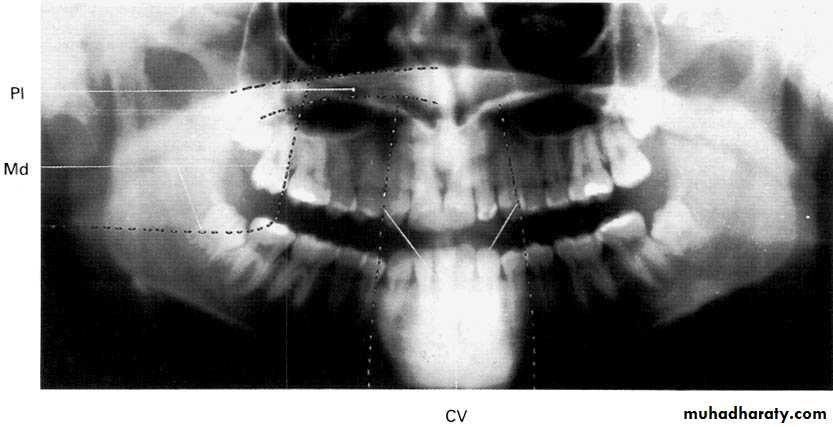

Panoramic Radiography

A dental panoramic tomograph showing the main anatomical ghost or artefactual shadows drawn in on one side of the radiograph, PI — palate, Md — mandible, CV — cervical vertebrae.